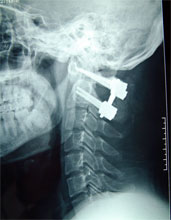

全麻,头颅牵引下手术体位           椎弓根螺钉钢板内固定已经安放好,寰枢关节融合术

行椎弓根螺钉钢板内固定,寰枢关节     术后3天患者即下地活动,肢体感觉、肌肉力量开始恢复。

融合术后,寰枢关节不稳脱位已经复位